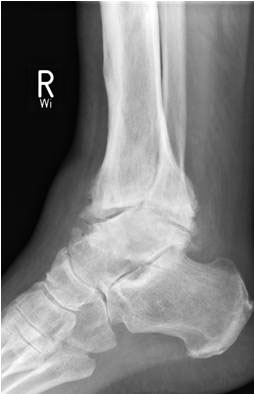

• Primäre oder posttraumatische Arthrose des OSG und USG (Abbildung 1, Abbildung 2).

• Revision einer gescheiterten Fusion des OSG/ USG (Abbildung 3, Abbildung 4).